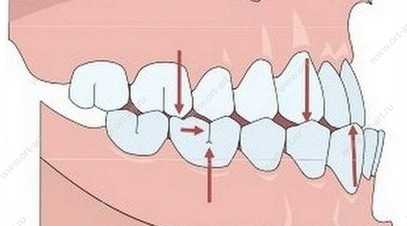

– нижние передние зубы выступают кпереди , относительно верхних передних зубов (или имеют тенденцию таким образом выступать).

Нижние передние зубы выступают кпереди.

Такое соотношение зубных рядов может варьироваться от так называемого прямого смыкания (прямого прикуса), когда передние верхние и нижние зубы смыкаются буквально «стык в стык», до обратной дизокклюзии, когда нижние зубы довольно сильно «выпирают» по отношению к верхним, с образованием сагиттальной щели.